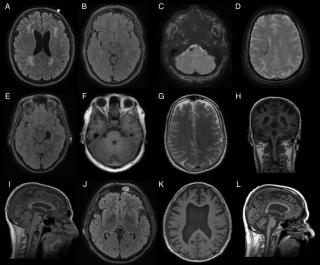

Дополнительные трудности для определения сроков формирования гематомы создают повторные кровоизлияния в ее содержимое. Частота изоплотных гематом колеблется от 5% до 25% [1]. Диагноз изоплотной субдуральной гематомы основывается на ее вторичных признаках, к которым относятся сдавление бокового желудочка, облитерация или медиальное смещение конвекситальных субарахноидальных борозд и дислокация срединных структур. Особенно трудны для лучевой диагностики двусторонние изоплотные субдуральные гематомы, когда единственным диагностическим признаком является уменьшение размеров боковых желудочков. В литературе описан симптом «заячьих ушей» при двусторонних субдуральных гематомах, характеризующийся сближением передних рогов боковых желудочков и заострением их формы [1]. Характер изображения субдуральных гематом при КТ и МРТ зависит от стадии разрешения кровяного сгустка или его организации. В острой стадии субдуральные гематомы при КТ выглядят как гомогенно плотные внемозговые образования серповидной формы. Однако до 40% острых субдуральных гематом характеризуются гетерогенно повышенной плотностью, что отражает наличие не-свернувшейся крови, сыворотки, образовавшейся в результате ретракции кровяного сгустка, примеси цереброспинальной жидкости (ЦСЖ). С течением времени происходит лизис кровяного сгустка и организация гематомы с формированием ее капсулы. Далее плотность гематом по КТ постепенно понижается, и подострые субдуральные гематомы проходят стадию изоинтенсивности со структурами головного мозга в период от нескольких дней до нескольких недель после травмы.

Хронические субдуральные гематомы представляют собой инкапсулированные образования с ксантохромным содержимым, иногда с дольчатой структурой. Плотность их в неосложненных случаях гомогенно низкая, но повторное кровотечение в полость гематомы приводит к гетерегонному ее изменению, что наблюдается как в капсуле, так и в самой гематоме. Магнитно — резонансные признаки субдуральных гематом различны. Этапы эволюции субдуральных гематом во многом напоминают разрешение во внутри-мозговые гематомы. Исключения составляют хронические субдуральные гематомы, которые выглядят как изо — или гипоинтенсив-ные образования на томограммах в режиме Т1 отложения гемосидерина по контуру гематомы наблюдаются очень редко. При этом хронические гематомы характеризуются повышенной интенсивностью [3,4].

Определенное клиническое значение имеет размер оболочечной гематомы, объем которой можно достоверно определить при КТ и МРТ. Оболочечные гематомы объемом до 40 куб.см считаются небольшими, от 40 до 60 куб.см — средними, от 60-90 куб.см — большими и свыше 90куб.см — массивными. Субдуральные гематомы объемом более 50 мл сопровождаются развитием выраженного отека пораженного полушария и смещением срединных структур в сторону, противоположную гематоме. Кровоизлияния, имеющие меньший объем или возникающие в зоне противоудара, протекают без отека мозга.

В данной работе мы проиллюстрируем случай из практики, в котором нетрадиционная консервативная терапия привела к благоприятному исходу заболевания. Больной 65 лет, поступил в стационар с жалобами на слабость, онемение в левой руке и ноге, головокружение, головные боли, повышение АД, шаткость при ходьбе. Болен в течение двух месяцев. Со слов больного заболел 20.02. 2012г. Отмечалось повышение АД до 200/100 мм рт.ст., появилась слабость в левой руке и ноге, головокружение, шаткость при ходьбе. Осмотрен неврологом, лечился по поводу ишемического инсульта. Позже выяснилось, что в начале февраля в холодную погоду, подскользнувшись на льду, упал, ударился головой, потерял кротковременно сознание, затем отметил постепенно нарастающие головные боли, отмечалось повышение АД, состояние ухудшилось. Доставлен в неврологическое отделение Городского медицинского центра (ГМЦ) 28.03.2012г. (выписан 16.04.2012г). Д-З при поступлении: "Ишемический инсульт в бассейне правой средней мозговой артерии". 4.04.2012г. сделана КТ головного мозга. Обнаружили хроническую субдуральную (обширную) гематому правой гемисферы мозга, латеральную дислокацию влево, внутренного гидроцефалию, атрофиию мозга, мозжечка. Костно деструктивных изменений не выявлено.

Нейрохирургом рекомендовано было оперативное лечение в отделении нейрохирургии Национального медицинского центра (НМЦ) РТ, от которого родственики и сам больной категорически отказались. Проводилась де-гидратационная терапия, нейропротекция , рассасывающая терапия, вазоактивные препараты. Выписан с улучшением, ходит с поддержкой, парез и гемиатаксия уменьшились. Амбулаторно в течение 4 месяцев получил 5 курсов препаратов вышеупомянутой схемы лечения. Неврологическая симптоматика почти полностью нивелировалась. Головные боли и головокружение не беспокоят. При обследовании : на МРТ от 16.04.12 г: (в день выписки) в субарахноидальном пространстве правого полушария определяется хроническая субдуральная гематома размером 20-94147, смещающая срединные структуры влево на 5мм. МРТ от 23.08.2012 г. (после нескольких курсов консервативной терапии в амбулаторных условиях): определяется в субарахноидальном пространстве правого полушария мозга наличие гематомы 10 мм в поперечнике, 73мм в передне — заднем размере. По сравнению с предыдущими данными МРТ, отмечается выраженное уменьшение гематомы в размерах. Анализируя подобный исход заболевания при наличии массивной субдуральной гематомы без оперативного вмешательства, можно предположить, что атрофический процесс в мозгу, возрастные изменения ткани мозга по типу энцефалопатии, невыраженный отек мозга способствовали благоприятному исходу заболевания. Согласно литературным данным, иногда возможно консервативное ведение указанных больных под контролем КТ или МРТ, особенно, если смещение не превышает более 5 мм [2].